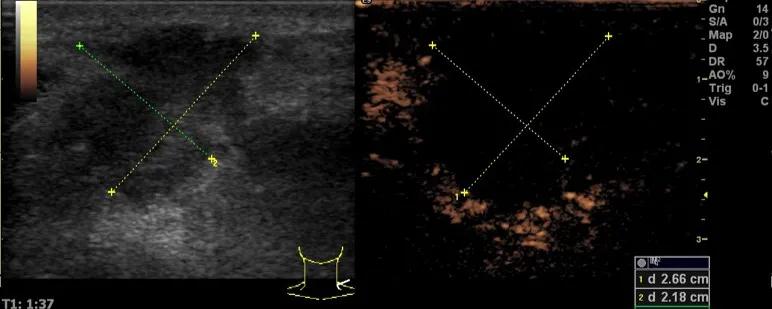

第5例是乳腺癌的患者,右乳恶性肿瘤术后化疗后1年出现淋巴结转移,患者基本情况差,拒绝放化疗,行局部热消融后也实现充盈缺损,术后一个月强化信号消失。

(病例5图例)